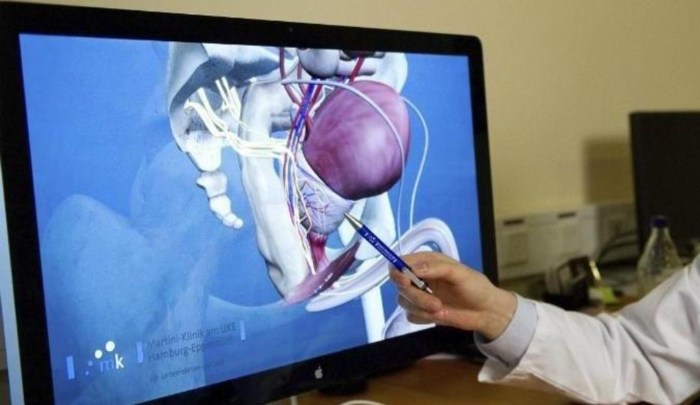

Comer champiñones ayuda a prevenir el cáncer de próstata

El cáncer de próstata es una de las causas principales de muerte entre los hombres, por lo que se recomienda un examen de próstata anual a partir de los cincuenta años, esto junto a una dieta equilibrada y ejercicio disminuyen el riesgo de desarrollar cáncer de prostata. Otra acción que puede ayudar a disminuir el … Continuar leyendo Comer champiñones ayuda a prevenir el cáncer de próstata

Cuándo se debe checar la próstata

La próstata es una glándula masculina que ayuda a producir el semen, el líquido por el cual se transportan los espermatozoides, la próstata rodea al conducto que lleva la orina desde la vejiga hasta el exterior del cuerpo. La próstata de una persona jóven es del tamaño de una nuez pero con la edad esta … Continuar leyendo Cuándo se debe checar la próstata

¡Ojo hombres! A partir de esta edad deben realizarse el examen de próstata

La salud es uno de los mayores privilegios del ser humano, pero que muchos no valoran al llevar un ritmo de vida que en nada favorece para mantener el cuerpo sano. Los hombres, por ejemplo, suelen ser algo obstinados y no acudir al médico, hasta que de plano, se sienten sumamente mal. No obstante, es … Continuar leyendo ¡Ojo hombres! A partir de esta edad deben realizarse el examen de próstata